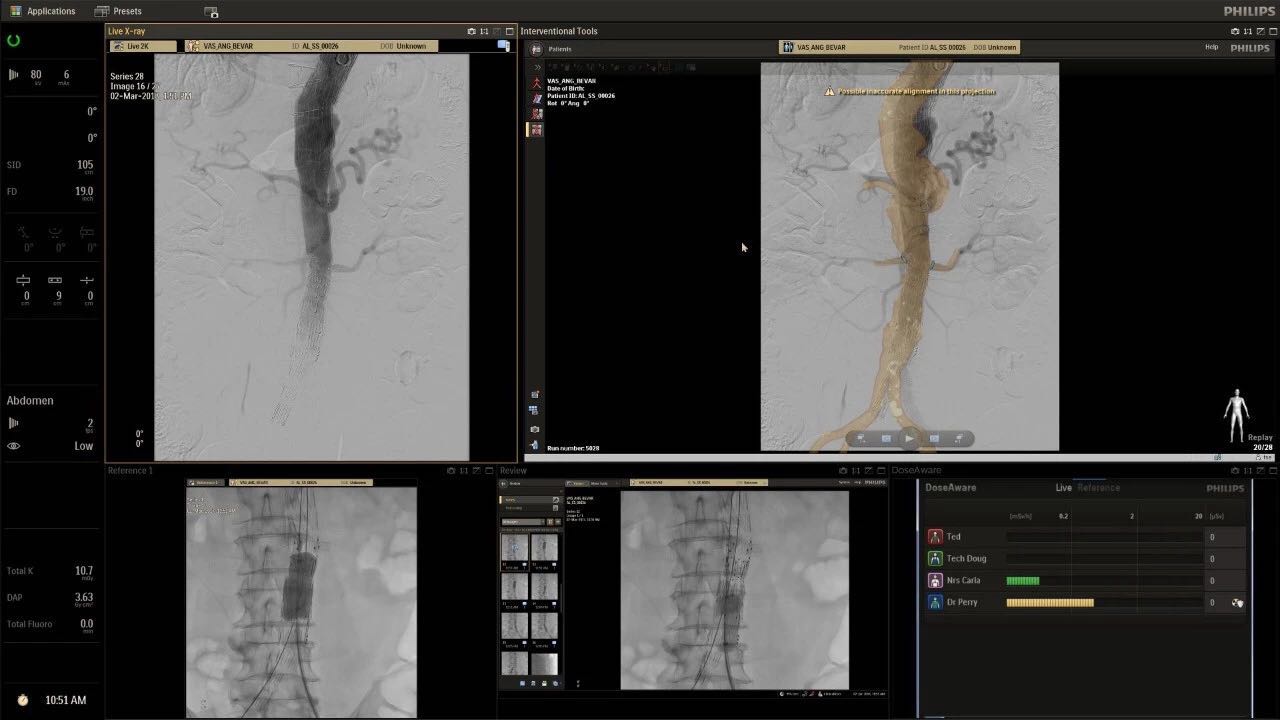

在日益復(fù)雜的干預(yù)期間,臨床醫(yī)生需要快速、輕松地可視化關(guān)鍵解剖結(jié)構(gòu)并確定手術(shù)過(guò)程中患者的變化。2019年1月17日,飛利浦宣布推出采用FlexArm的Azurion 7 C20,旨在提高圖像引導(dǎo)程序的定位靈活性。

帶有FlexArm的Azurion 7 C20 包含一系列創(chuàng)新技術(shù),使臨床醫(yī)生可以更輕松地在整個(gè)患者身上進(jìn)行二維和三維成像。當(dāng)臨床醫(yī)生移動(dòng)系統(tǒng)時(shí),圖像光束自動(dòng)保持與患者的對(duì)準(zhǔn),允許更一致的可視化并使他們能夠?qū)⒆⒁饬性谥委熒稀?/span>

(FlexArm C型臂可以沿著工作臺(tái)的兩側(cè)提供偏心成像。這允許醫(yī)生在左臂或右臂上進(jìn)行徑向進(jìn)入病例,完全或部分伸展,而無(wú)需移動(dòng)患者或樞轉(zhuǎn)桌子。X射線束與手臂保持對(duì)齊,以促進(jìn)其整個(gè)長(zhǎng)度的平滑導(dǎo)航,而無(wú)需進(jìn)行持續(xù)調(diào)整。)

飛利浦表示,采用FlexArm設(shè)計(jì)的Azurion 7 C20可提供卓越的靈活性和直觀的控制。該系統(tǒng)由智能運(yùn)動(dòng)引擎驅(qū)動(dòng),可在八個(gè)不同的軸上移動(dòng),所有這些軸均由其單個(gè)“Axsys”控制器控制。臨床醫(yī)生的模擬測(cè)試表明,該系統(tǒng)有可能顯著減少患者,工作人員和設(shè)備的重新定位,從而改善微創(chuàng)手術(shù)的可及性,包括通過(guò)患者手腕進(jìn)入身體的手術(shù)(橈動(dòng)脈入路),并降低患者的風(fēng)險(xiǎn)。無(wú)意中拔出電線和管子,以及節(jié)省大量時(shí)間。該系統(tǒng)非常適合混合手術(shù)室(OR),可滿足一個(gè)房間內(nèi)的多種專業(yè)需求,例如手術(shù)和血管內(nèi)手術(shù)的組合。

(FlexArm在不少于8軸的情況下旋轉(zhuǎn),從而創(chuàng)建幾乎無(wú)限的靈活性來(lái)執(zhí)行成像,從頭部到腳部在左側(cè)和右側(cè)進(jìn)行2D和3D可視化。圖像光束保持與患者對(duì)齊,允許在旋轉(zhuǎn)或角度期間更好地可視化解剖結(jié)構(gòu)。使用Axsys運(yùn)動(dòng)控制系統(tǒng)輕松操作支架。)